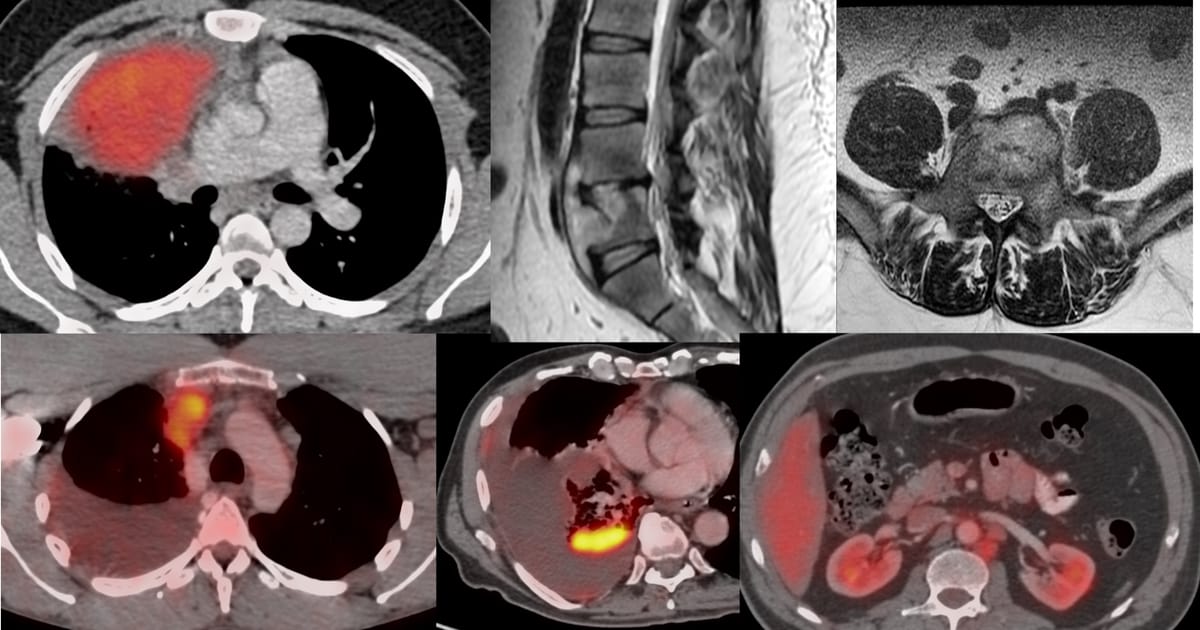

Current Case:

59-years old with fever and non-resolving consolidation

What would be your approach?

The video below describes the case and the reason for performing a biopsy parallel to the vessels and not perpendicular